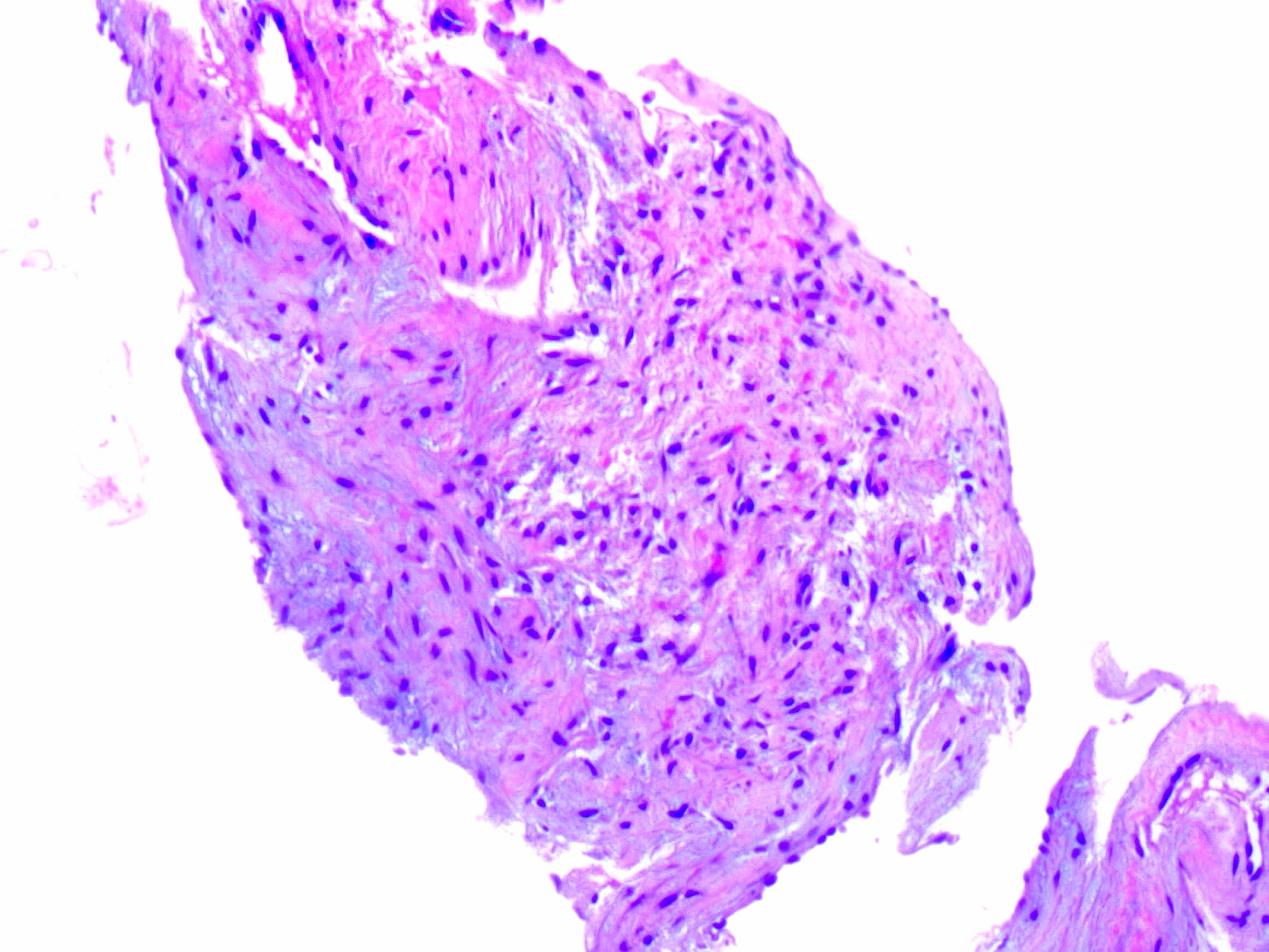

患者男,57岁,2020年11月30日因脑出血就诊于当地医院,治疗期间腹胀突然加重,随后转诊至本院。患者有轻度腹胀10余年病史,从未做过任何相关检查,也未服用过任何药物,否认肝炎、结核等病史。入院查体:患者使用气管插管和呼吸机进行辅助通气,全身皮肤黏膜黄染、可见散在瘀斑,严重腹胀,腹部有轻压痛,体格检查及超声检查结果均提示肝下界在前正中线上达脐水平线下8 cm处(图 1),脾脏未触及,双下肢中等程度水肿。实验室检查发现许多异常,包括红细胞2.52×1012/L、血红蛋白82 g/L和血小板63×109/L,白蛋白34.6 g/L,凝血酶原时间15.6 s,活化部分凝血酶时间46.8 s,纤维蛋白原0.62 g/L,D-二聚体31.09 mg/L等。乙肝抗原、丙型肝炎病毒抗体检测均为阴性,血清肿瘤标志物均在正常范围内。超声检查提示肝脏体积巨大,肝脏内探及大小不一的不均质回声团,边界不清。普通CT扫描检查提示:肝脏体积明显增大(约44.06 cm×38.46 cm×10.21 cm),肝叶比例失调,肝实质密度不均。入院3 d后,为了获取明确诊断,对患者的肝脏进行多部位穿刺活检后送病理学检查,诊断结果为:肝海绵状血管瘤(图 2)。该检查导致了腹腔内活动性出血,肝功能急剧下降等意料之外的严重后果。笔者随即对患者行腹腔血管造影及介入栓塞术止血治疗,同时使用药物改善肝功能,患者病情恢复平稳。入院15 d后,由于患者多次血常规检查提示外周血全血细胞减少,又给予骨髓穿刺检查排除血液系统疾病。入院20 d后,我们对患者进行腹部核磁共振扫描来评估病情,但仍未明确诊断。于是又进行腹部增强CT扫描检查,结果提示肝脏体积明显增大,密度不均,全肝弥漫分布片状及斑片状低密度灶,增强扫描病灶未见明显强化,病灶间散在正常强化肝组织,符合弥漫性海绵状肝血管瘤诊断(图 3)。结合所有检查及患者临床表现,患者最终被诊断为弥漫性肝血管瘤病合并卡萨巴赫-梅里特综合征。肝移植被认为是本例患者可以根治性治疗的唯一办法,但考虑到他近期的脑出血病史及身体情况而没有进行手术。笔者给予患者积极的对症治疗,包括使用药物改善肝功能,输注新鲜的冰冻血浆、冷沉淀凝血因子、血小板等。不幸的是,该患者在确诊1个多月后死于多器官功能衰竭。

| 图 2 组织病理学检查 |